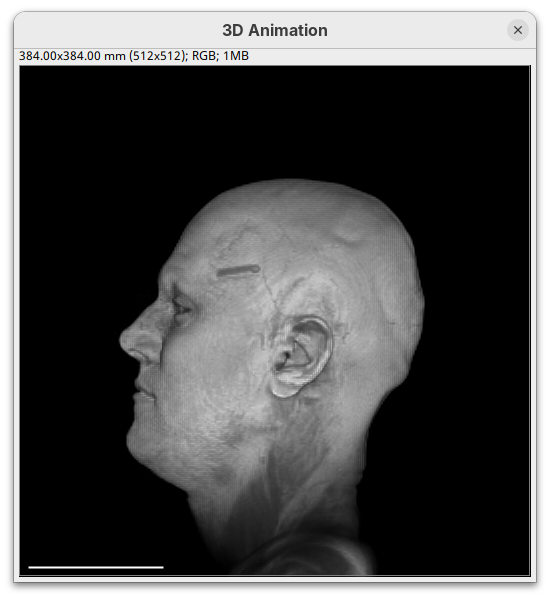

Two new windows will open: 3D Animation with the initial rendering of the data and Interactive Raycaster with all the fields to control the rendering parameters.

Contrast

Adjusting the intensity and alpha values is the most impactful way to improve the 3D rendering. With the intensity setting we can define which pixel value in the image corresponds to total black (minimum) and which corresponds to total white. It’s the same as in the standard Brightness & Contrast tool. By default, 3Dscript will load these values from the original stack. In this case, it loaded min=3 and max=521.

The blue line represents the alpha values. In 3D rendering, a pixel has a transparency value linked to its intensity. The alpha min defines the value for full transparency and the max the value for full opacity.

- Set the alpha

minto250.

This will make darker pixels more transparent and information gets lost.

- Set it to

0.

By default 3Dscript sets the gamma value of alpha to 2.0. That’s a good default for fluorescence microscopy (see the next dataset below), but since this is MRI data, we need to tweak it a little differently.

- Set the alpha gamma value to

1.0.

Note that this improves the visualization as the head’s surface becomes better visible.

- Now set the alpha

maxto250.

The surface will become even more solid because we are defining that pixels that have a value above 250 will be fully opaque.